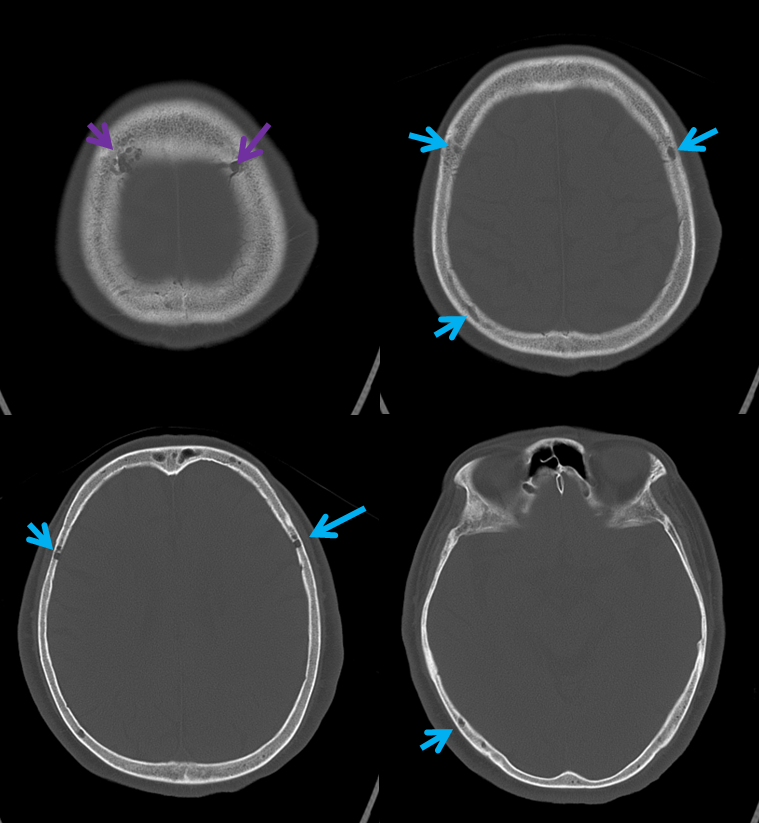

All of the above anatomic knowledge can become very useful in evaluation of venous thrombosis. Numerous collateral pathways develop in this setting attempting to compensate for the loss. The most dramatic cases usually involve the largest channel — the superior sagittal sinus. In this case, a man presented with what initially was thought to be vasculitis-related brain hemorrhage. Subsequent workup led to an angiogram, where sagittal sinus thrombosis with extensive trans-cerebral and trans-osseous emissary vein collateral channels was seen. In retrospect, these findings were present on the patient’s earlier contrast MRI. “Venovibe” or other contrast-enhanced MR venograms can very sensitive, particularly when interpreted with the appropriate index of suspicion. Noncontrast 2-D time of flight MRV I consider to be next to useless as a problem-solving technique. Any thin-slice postcontrast T1 study is vastly superior.